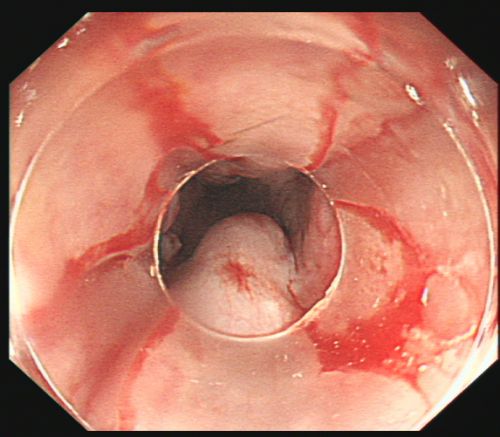

省医岳麓山院区综合内科彭娅主任团队为患者施行胃镜下食管曲张静脉套扎及硬化剂注射治疗。

由于血管压力高,手术风险大,术中发生大出血、窒息及异位栓塞的风险非常高。综合内科主任彭娅反复与家属沟通取得理解配合后,为易某实施改良后内镜下止血技术——食管曲张静脉套扎+硬化剂注射治疗。所幸手术过程顺利,术后继续予以降门脉压力、护胃、减轻腹水、维持内环境稳定等对症支持治疗。经过积极治疗,患者病情趋于稳定,已恢复饮食,精神状况好转,于215日出院。